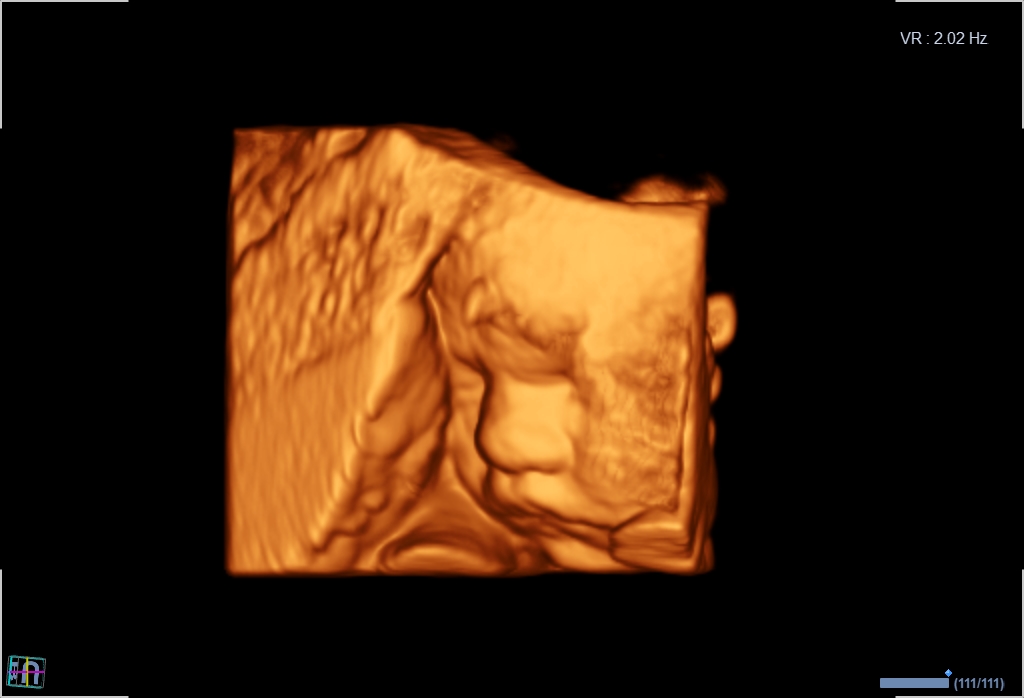

3D/4D-Ultraschall für Schwangere

Ergänzende Sonographie als Wahlleistung

Seit März 2019 steht ein neues 3D/4D-Ultraschallgerät für faszinierende Eindrücke von Ihrem Baby zur Verfügung.

Außer den Fotos können auch 3D/4D Viedeoclips gemacht und auf einem USB-Stick gespeichert werden. So können die Bilder und Clips jederzeit angesehen werden.